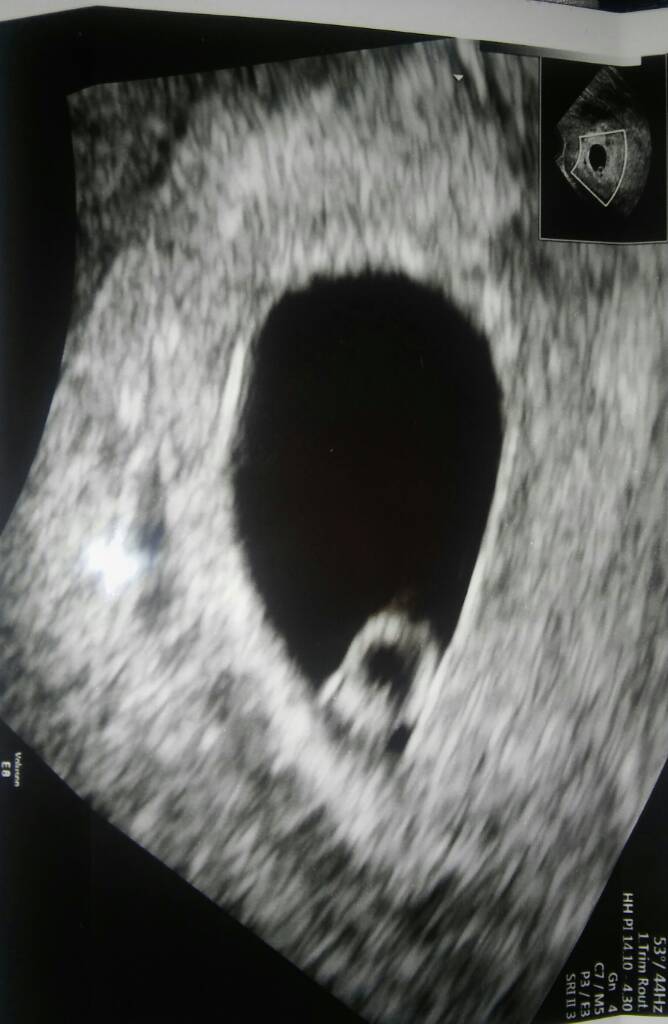

To nasze Maleńkie Szczęście :) Serduszko pięknie bije :) Z Om 6t3d z usg 6t0d :) Dziękuję za wszystkie kciuki, oby tak dalej :)

Załączniki

• 1458586806574.jpg

1458586806574.jpg

54,3 KB · Wyświetleń: 113

Martusia fantastycznie! Mam niemal identyczne zdjecie z tego okresu i tez usg dwa czy trzy dni mlodsze niz OM! Teraz ide 31.03 juz nie moge sie doczekac :)